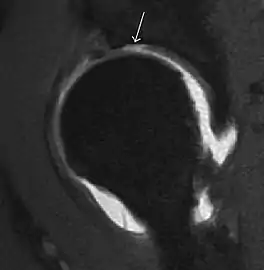

Synovial chondromatosis can be confidently diagnosed by X-ray when calcified cartilaginous chondromas are seen. However, other synovial proliferative processes, such as pigmented villonodular synovitis, require MRI for accurate diagnosis, although noncalcified synovitis can be suspected in radiographs by indirect signs, such as soft tissue swelling and/or erosions in the femoral head, femoral neck, or acetabulum (Figure 7).[1]

Figure 7:

Axial CT image of pigmented villonodular synovitis eroding the posterior cortex of the femoral neck.[1]

In synovial proliferative disorders, MRI demonstrates synovial hypertrophy. In the case of PVNS, characteristic foci of low signal intensity related to hemosiderin deposition are better seen on gradient echo T2* images (Figure 7). In the case of synovial osteochondromatosis, the synovial hypertrophy is accompanied by intermediate signal cartilaginous loose bodies and/or low signal calcified loose bodies.[1]